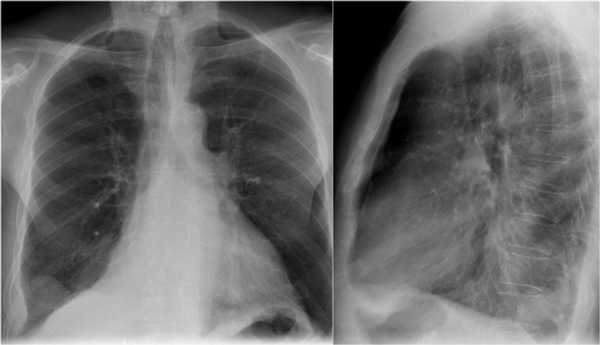

Ателектаз верхней доли правого легкого.

Оцените ниже лежащие изображения, а после продолжите чтение.

- Трехгранное затенение.

- Подъем правого корня легкого

- Облитерация загрудинного пространства (указано стрелкой).

На ПЭТ/КТ визуализируется опухоль легкого с обструкцией правого верхнедолевого бронха, как следствие ателектаз верхний доли правого легкого.